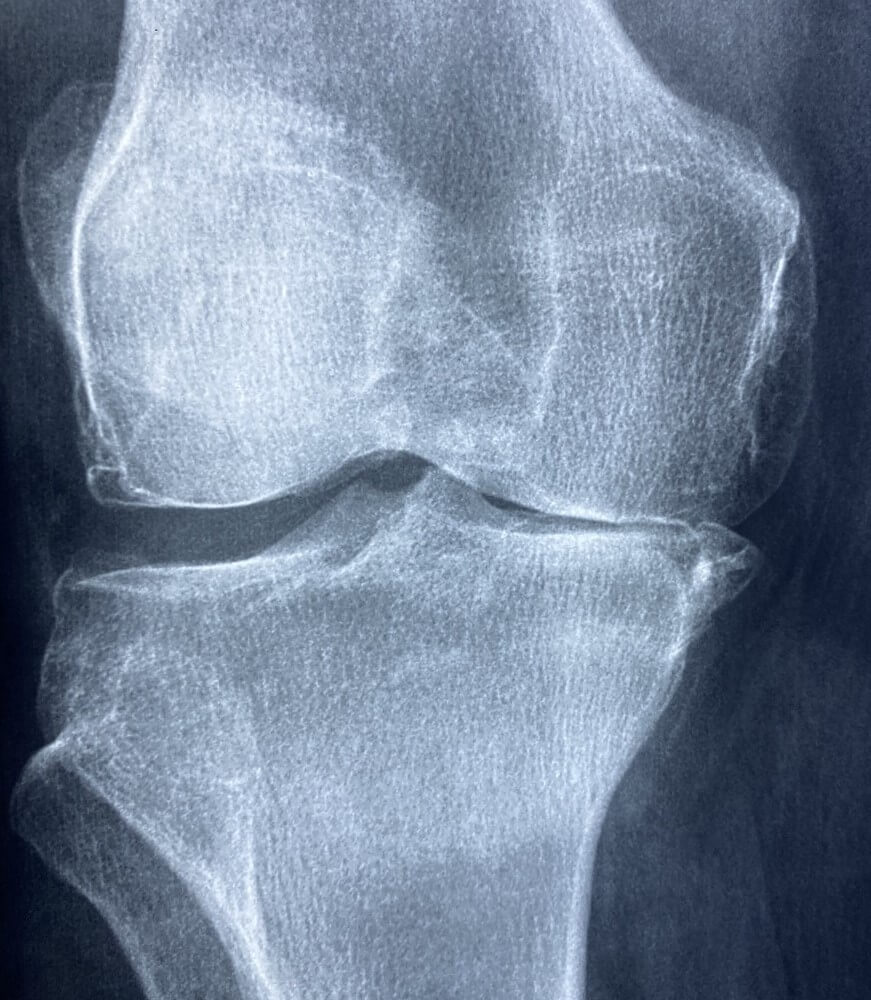

관절 연골이 점진적으로 분해되는 것을 특징으로 하는 이 상태는 전 세계적으로 수백만 명에게 영향을 미칩니다. 주로 노화된 개인에게 영향을 미치지만 유전, 일반적인 부상 또는 썩음과 같은 다채로운 요인으로 인해 젊은 성인에게도 영향을 미칠 수 있습니다. 골관절염의 증상을 이해하는 것은 환자가 그 상태를 효과적으로 관리하고 삶의 질을 향상시키는 데 매우 중요합니다.

골관절염의 또 다른 일반적인 증상은 흔한 덩어리와 여린 마음입니다. 연골이 닳으면서 뼈가 서로 마찰하여 염증을 유발할 수 있습니다. 이 염증은 영향을 받은 관절 주위가 부어오르게 하여 평소보다 더 커 보입니다. 또한 해당 부위로의 혈액 유입이 증가하여 관절이 만져지면 따뜻함을 느낄 수 있습니다. 붓기와 함께 관절이 부드러워져 만지거나 압력을 가하는 것이 고통스럽습니다. 실제로 부드러운 만지면 불편함이 촉발되어 골관절염으로 사는 데 전반적인 부담이 가중될 수 있습니다.

골관절염은 뼈의 끝을 고치던 방어 연골이 시간이 지남에 따라 닳아 없어지면서 발생합니다. 그 결과 뼈가 서로 마찰하면서 영향을 받은 관절에 통증, 붓기, 경직이 발생합니다. 많은 경우 골관절염을 관리하는 첫 번째 단계는 상태와 진행 상황을 이해하는 것입니다. 여기에는 류마티스 전문의나 정형외과 전문의와 같은 의료 전문가와 상담하는 것이 포함되며, 의료 전문가는 소중한 인식과 지침을 제공할 수 있습니다. 또한 건강한 체중을 유지하고 규칙적인 운동을 하는 것과 마찬가지로 삶의 변화의 중요성에 대해 스스로 교육하는 것은 골관절염을 효과적으로 관리하는 데 매우 중요합니다.